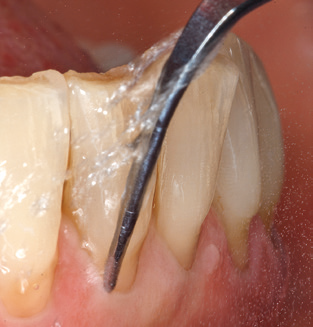

Good illumination of the working field facilitates the process considerably. The system used by the authors achieves this thanks to a 5x LED ring integrated in the handpiece. Naturally, a range of working tips for different indications is also offered. A straight, universally employable tip is the basic instrument required for machine cleaning of natural teeth (Fig. 5a and b). Curved tips, which allow access to exposed furcations, are also available for hard-to-reach areas in the posterior region (Fig. 6).

Fig. 4: Flexible probes with millimetre markings are recommended for the probing of dental implants (e.g. Colorvue Kit PCV11KIT6, Hu­Friedy). – Fig. 5a and b: A straight working tip (1P, W&H Dentalwerk Bürmoos GmbH) is a suitable instrument for use on all natural teeth. – Fig. 6: Curved working tips (3Pr/3Pl, W&H Dentalwerk Bürmoos GmbH) lend themselves to the processing of difficult-to-reach areas of the tooth and root surfaces (e.g. furcations). – Fig. 7: The tapered, hexagonal implant cleaning tip (1I, W&H Dentalwerk Bürmoos GmbH) permits atraumatic and efficient cleaning of the crown and abutment surfaces. – Fig. 8: Titanium and carbon curettes are suitable instruments for the manual cleaning of the implant surfaces.